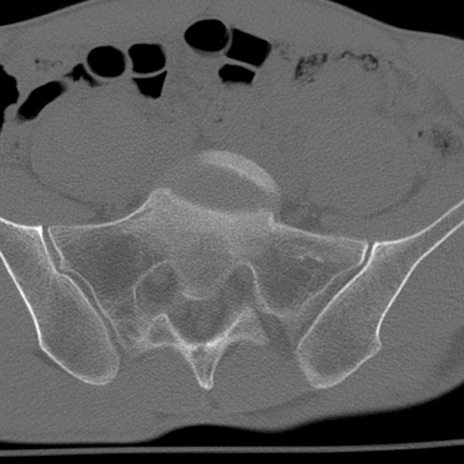

腰椎CT

冠状断像